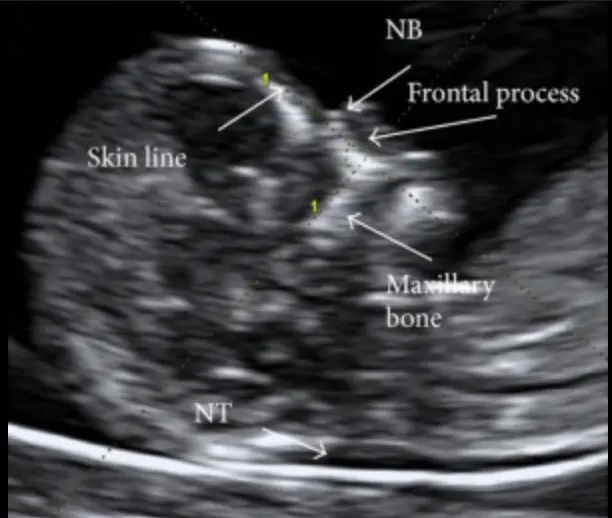

The days of considering the 12 week ultrasound as just a screening test for chromosome abnormalities (like Down syndrome) are long gone. Advances in ultrasound technology mean that we can start to examine your baby’s anatomy much sooner than in the past. The first trimester anatomy scan is performed between 12 and 14 weeks gestation and is an important option to check the development of your baby no matter your choices for chromosomal screening.

During this ultrasound we will check your baby’s heart beat, growth as well as the due date for your pregnancy. Our dedicated team will also check:

- Anatomy of your baby

- Nuchal Translucency

- Placental location and ovaries

With advances in ultrasound technology, your baby’s anatomy can be seen in great detail between 12 and 14 weeks gestation. It is now possible to see your baby’s arms, legs, fingers, and toes as well as skull, heart, brain, stomach, and kidneys.

During this ultrasound we undertake additional tests to screen your baby (if requested) for you, your cervical length, and risks of developing pre-eclampsia. This involves:

- Chromosomal anomalies by measuring the nuchal translucency thickness

- Risk of pre-eclampsia by measuring the uterine artery blood flow

- Assess for pre-term birth through measuring the length of the cervix

Whether you choose to have screening for chromosomal abnormalities or not, the 1st trimester anatomy scan can provide much more information on your growing baby.